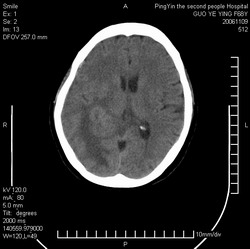

郭*,61岁 ,头痛半月并有复视

右侧颞枕叶见形态不规则等密度灶,灶周可见水肿灶,考虑:1、胶质瘤?2、转移瘤?建议做增强或mri检查

右侧颞枕叶见形态不规则等密度灶,中心见低密度影,灶周可见水肿明显,右侧脑室受压变窄,考虑胶质瘤或转移瘤。请作增强或mri检查

平扫观察右侧至少有3个结节伴周围水肿,首先考虑转移。先查肺部吧。

右侧颞枕叶示结节状影,外缘示片状低密度影,相应脑室未见明显受压,考虑转移瘤。

右侧脑实质内多发结节影并指状水肿.

意见:考虑多发转移瘤.

右侧颞枕叶见多个形态不规则等密度灶,中心见低密度影,灶周可见水肿明显,右侧脑室受压变窄,考虑转移瘤或胶质瘤。请作增强或mri检查